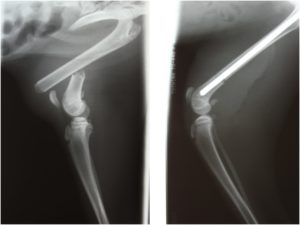

Case53 ピンニングを行った第2 4中足骨骨折の猫の1例 つつじヶ丘動物病院 東京都調布市の動物総合病院 一般診療 循環器科 腫瘍科など

上腕骨骨折の猫 住田動物病院 北九州市 小倉南区